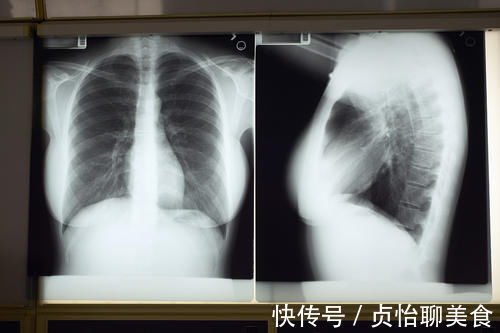

肺纹理增粗正常吗?有哪些原因会导致肺纹理增粗?

肺纹理增粗是一个主观判断:肺纹理增粗是一个很主观的描述,医生自己的经验,比如说他看过很多的胸片,大部分是肺纹理是某一个状态,然后看到另外一张胸片纹理比这个比大多数胸片要增粗一点,它就可以诊断肺纹理增粗。如果这一张胸片给另外一个医生看,他就不一定会诊断肺纹理增粗,因为在他的直觉里,这样的肺纹理是可以的。当然,如果是明显的、典型的肺纹理增粗,那绝大部分医生的判断是一样的。

良性(生理性)肺纹理增粗:在一些老年人、长期吸烟的人、相对肥胖的人,都有可能在拍片的时候提示肺纹理增粗。甚至这种肺纹理增粗可能与拍片机器曝光度、清晰度有关系。

病理性肺纹理增粗有哪些原因?前面提到过肺纹理指的就是支气管、动脉和静脉重叠的影子。所以被窝内增粗,也就是这三个结构出了问题。

支气管原因:各种病原体引起的支气管炎,支气管周围炎,支气管扩张都有可能导致肺纹理增粗。

肺动脉原因:肺动脉扩张、肺动脉充血,都会导致肺纹理增粗,常见的疾病包括各种左向右分流型先天性心脏病,比如房间隔缺损、室间隔缺损、动脉导管未闭,以及原发性肺动脉高压等。所以说肺动脉扩张大多数是心脏病。

肺静脉原因:心肺相连,正常肺静脉的血应该往左心房、左心室、主动脉方向流动,如果在这一方向出现了梗阻,比如说二尖瓣狭窄、二尖瓣关闭不全、主动脉瓣狭窄、主动脉瓣关闭不全、主动脉弓缩窄等原因,就会使得肺静脉的血液淤积过多,导致肺静脉扩张,从而出现胸片上的表现:肺纹理增粗。这样看来肺静脉扩张大部分也都是心脏病。